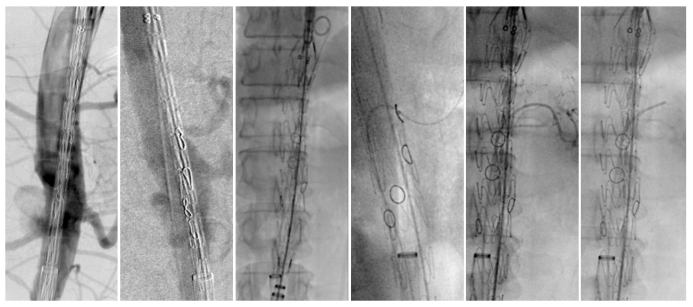

★ Case1:男,60岁,假性动脉瘤

★ Case2:男,69岁,腹主动脉瘤。全程束径。

★ Case3:术中束径丢失,如何处理补救?男,72岁,胸腹主动脉瘤。

在一例胸腹主动脉瘤手术中,发生了罕见的“束径丢失”(束径导丝意外脱出),导致支架提前贴壁。面对危机,团队并未慌乱,而是迅速采取补救措施:

立即建立生命线: 从上肢紧急穿刺置入6F鞘,优先超选并保护SMA。

逆向思维,化险为夷: 在SMA这条“生命线”保障下,从容地从股动脉重新尝试超选其他分支,最终成功完成手术,避免了开腹手术。